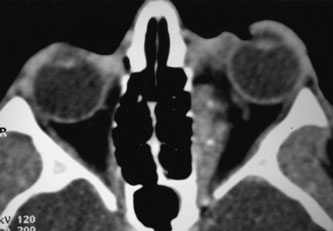

Investigations

There are no pathognomonic ultrasonography, CT, or MRI findings. A-scan ultrasonography shows well-delineated regular structures with low internal reflectivity and minimal attenuation owing to the congested pools of blood in the dilated veins. Doppler demonstrates flow within the lesion.58 Computed tomography may show abnormally dilated, irregular veins with uniform contrast enhancement or, when there has been hemorrhage, multilobular lesions.58 As the VFM may not be visualized when collapsed, direct coronal scans should be obtained in the prone position or during the Valsalva maneuver to distend the lesions (Fig. 14). Spiral CT with a single breath-holding technique may be useful in confirming an increase in size of the lesion during the Valsalva maneuver.104 The majority of venous malformations typically occupy the superomedial orbit in the area of the superior ophthalmic vein, followed by the inferolateral quadrant.95,104 In their study of 158 patients with NFM and VFM, Wright and colleagues found 45% with phleboliths.95 Enlargement of the affected orbit also may be seen.95 Obtaining MRI scans before and during a Valsalva maneuver may show distensibility, and uniform enhancement occurs.58 Venography is seldom used now because of the availability of other imaging modalities. Carotid angiography may demonstrate the VFM and can detect venous enlargement consequent to arteriovenous shunting.

Fig. 14. Orbital venous flow malformation. Axial computed tomography scan showing an ill-defined, dense, inhomogeneous orbital lesion with the patient in a supine position (A). Note the phlebolith, which indicates venous stagnation. As the venous flow malformation distends with the patient in the prone position, the lesion enlarges (B). (Courtesy of Dr. John V. Linberg, University of West Virginia, Morgantown, WV)